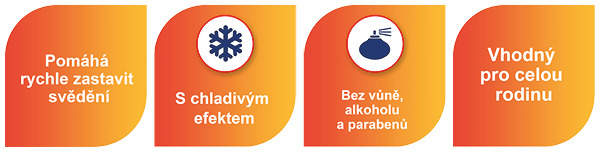

Fenistil gel rychle proniká do kůže, neobsahuje alkohol, parfémy ani barviva a je vhodný k použití pro děti i dospělé. U kojenců a malých dětí se vyhněte použití na rozsáhlých oblastech kůže, zejména pokud jsou na ní otevřené a zanícené rány.

Používá k úlevě od podrážděné svědivé pokožky, jako jsou vyrážky, kopřivka, bodnutí hmyzem, popáleniny od slunce a pomáhá i na mírné povrchové popáleniny. Fenistil gel obsahuje účinnou látku spadající do skupiny léčiv označovaných jako antihistaminika a má i chladivý účinek.